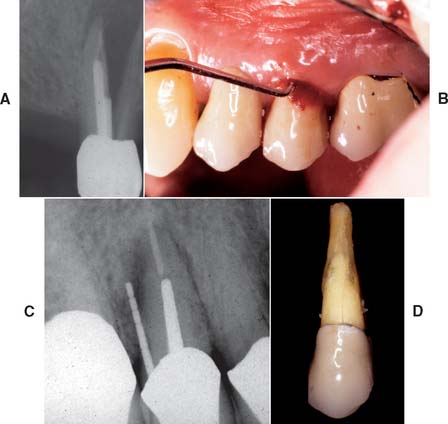

If the patient has several endodontically treated teeth that have been restored with posts and cores and with fixed prostheses, the possibility of root fracture should be considered, especially for teeth that were internally weakened as a result of endodontic treatment in conjunction with oversized posts of suboptimal length. If a fracture has occurred, the tooth is almost invariably lost, which can significantly complicate follow-up treatment, especially if it involves an abutment tooth for an FDP (Fig. 32-18).

A loose retainer usually indicates inadequate tooth preparation, poor cementation technique, or caries. In this case, the tooth requires repreparation and a new prosthesis. Sectioning the prosthesis rather than attempting to remove it intact is often the best policy (Fig. 32-25).

Fig. 32-25 Removal of an existing crown by sectioning. A, This cantilevered partial fixed dental prosthesis required replacement for esthetic and periodontal reasons. B, The restoration is carefully sectioned, with the initial cut through the ceramic just to the metal. It is easiest to do this on the facial and incisal surfaces. C, The goal is to cut through the metal just to the cement and follow the cement toward the gingival margin. D, The gingiva is displaced with an instrument and the crown carefully sectioned to the gingival margin (E). F, A suitable instrument (e.g., a cement spatula or sterilized screwdriver) is placed in the cut and gently rotated to force the halves of the crown apart. It may be necessary to section part of the lingual surface to facilitate this step. G, The abutment. Additional incisal reduction was necessary; the notch in the incisal edge is of no concern. H, Removed prosthesis.

(Courtesy of Dr. D. H. Ward.)